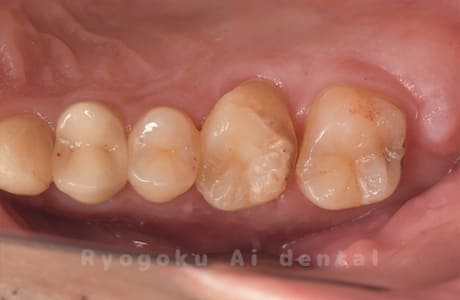

Case26

歯軋りが原因で奥歯を割ってしまった患者様です。下の親知らずを移植し、その際にサイナスリフトを行いました。問題なく経過し、患者様も大変満足されていました。